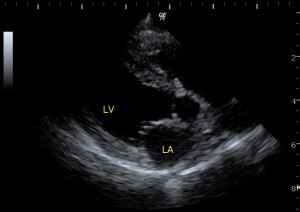

僧房弁閉鎖不全の子の心臓の超音波画像です。

上の画像と見比べるとLAの部分が大きくなっています。これはLVからLAに血液が逆流して起こります。LAの部分に血液が溜まって圧力がかかっていくのでLAが大きくなっていきます。